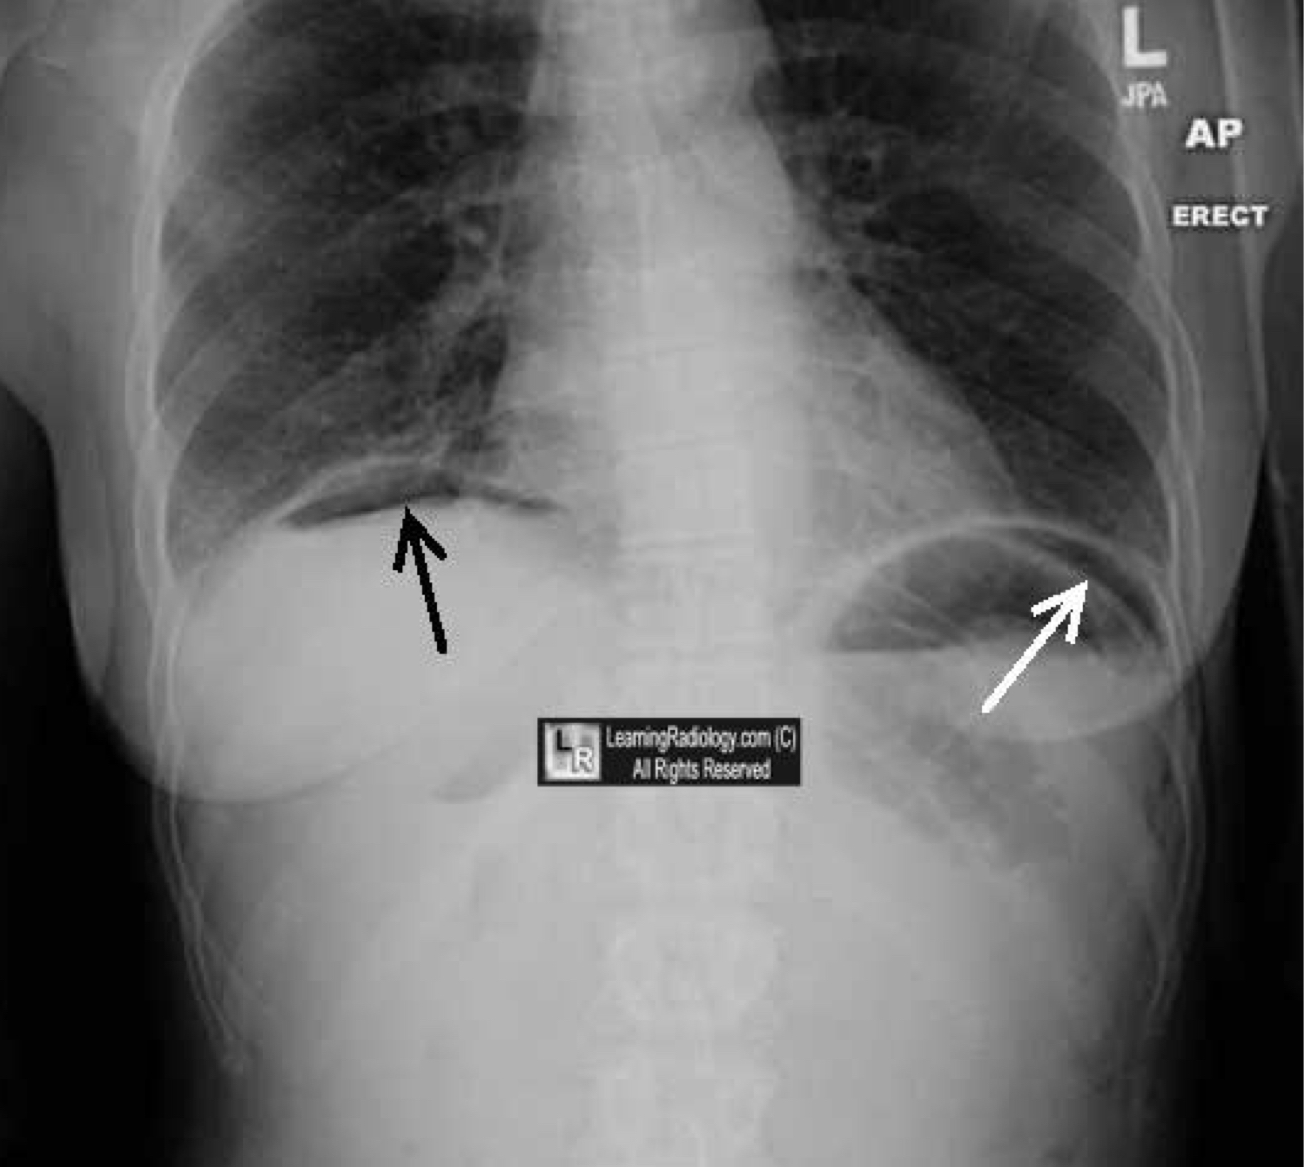

What is indicated by the top left arrow?

pneumoperitoneum

What is indicated by the top right arrow?

air in the stomach (normal)

What is indicated by the black arrow?

What is indicated by the white arrow?

(see double line in the stomach shadow area)